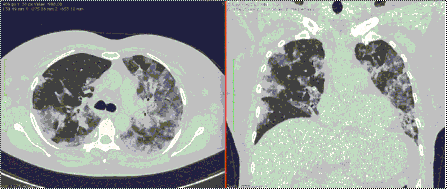

4.3. ЛУЧЕВАЯ ДИАГНОСТИКА COVID-19

Методы лучевой диагностики применяют для выявления COVID-19 пневмоний, их осложнений, дифференциальной диагностики с другими заболеваниями легких, а также для определения степени выраженности и динамики изменений, оценки эффективности проводимой терапии.

КТ имеет высокую чувствительность в выявлении изменений в легких, характерных для COVID-19. Применение КТ целесообразно для первичной оценки состояния ОГК у пациентов с тяжелыми прогрессирующими формами заболевания, а также для дифференциальной диагностики выявленных изменений и оценки динамики процесса. КТ позволяет выявить характерные изменения в легких у пациентов с COVID-19 еще до появления положительных лабораторных тестов на инфекцию с помощью МАНК. В то же время, КТ выявляет изменения легких у значительного числа пациентов с бессимптомной и легкой формами заболевания, которым не требуется госпитализация. Результаты КТ в этих случаях не влияют на тактику лечения и прогноз заболевания при наличии лабораторного подтверждения COVID-19. Поэтому массовое применение КТ для скрининга асимптомных и легких форм болезни не рекомендуется. При первичном обращении пациента с подозрением на COVID-19 рекомендуется назначать КТ только при наличии клинических и инструментальных признаков дыхательной недостаточности (SpO2 < 95%, ЧДД > 22).